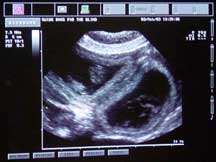

She has approximately 8 puppies inside her. This is a guess and things can change as she gets closer to her due date (Oct 30). The puppies are about an inch long. This was Alda's 5th week of pregnancy. |

These two images are photographs of the ultrasound monitor on the cart. As it was explained to me, the round dark blobs are the puppies in their individual sacks and the white fuzzy splotch in the dark blob is the puppy. While there we could see one of the puppy's heart beating. It was moving fast, creating a really fuzzy spot in the center of the fuzzy splotch. Doc said a typical puppy heart beat is 180 beats per minute. Alda's heart beat is 88 beats per minute, I just checked.